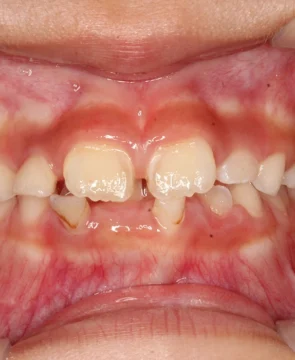

2026/03/17全体的な歯並びのがたつきが気になる9歳女児の矯正症例紹介 今回ご紹介する患者様は、全体的な歯並びのがたつきを気にされており、矯正検査後叢生Ⅰ級と診断いたしました。 治療前後の比較 矯正術前:正面 矯正術後:正面 矯正術前:右側 矯正術後:右側 矯正術前:左側 矯正術後:左側 矯正術前:上顎 矯正術後:上顎 矯正術前:下顎 矯正術後:下顎 矯正術前:前歯部あおり 矯正術後:前歯部あおり 矯正術前:オーバージェット 矯正術後:オーバージェット 主訴 全体的な歯並びのがたつきが気になる 治療期間 ・マウスピース矯正:3カ月 治療費用 66…